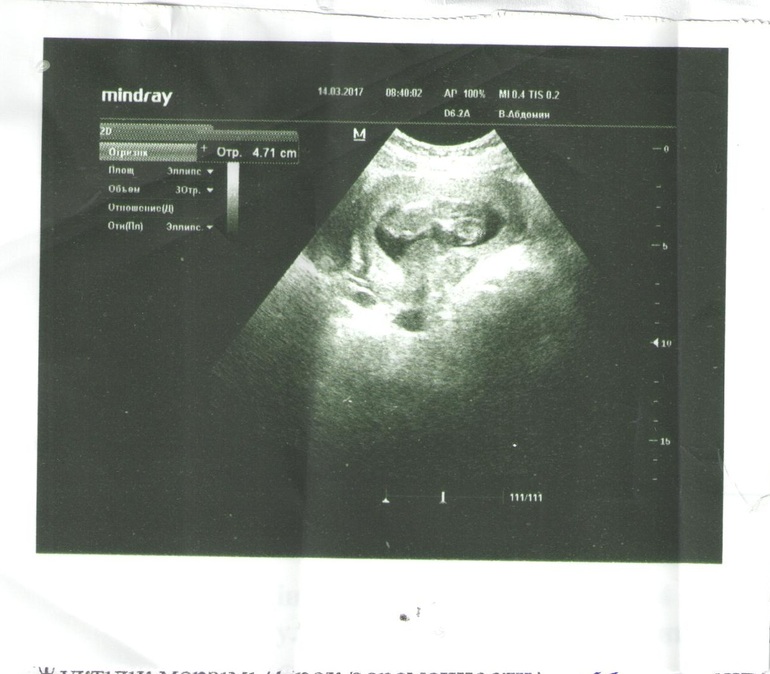

Спустя месяц после полного обследования, мне показали ЕГО на УЗИ и дали снимок моего малыша. О, Аллах, как же ты милостив и милосерден ко мне и моей семье. Твое создание носит внутри себя такое чудо. Насмотреться невозможно!

Здесь нам 11 недель 4 дня